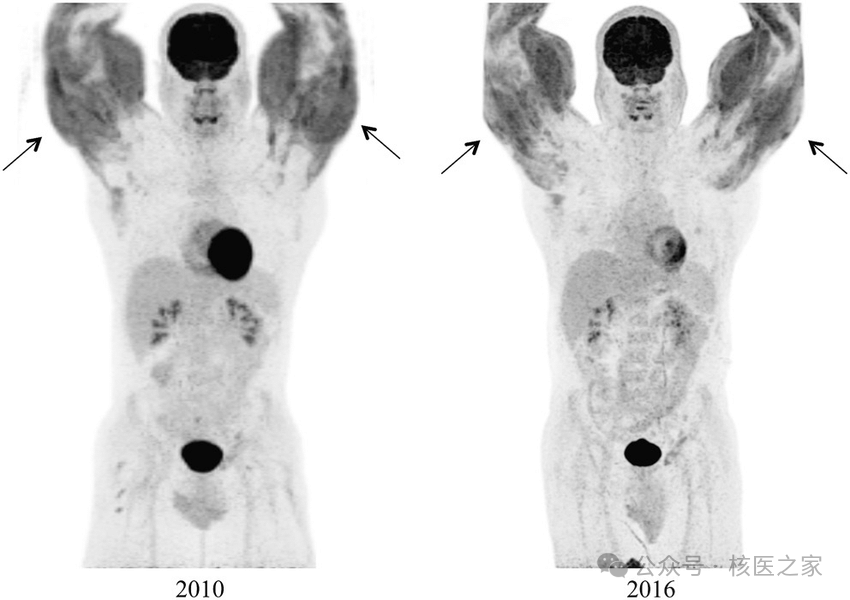

50岁黑色素瘤患者,行PET/CT检查前进行体育锻炼,导致双侧胸大肌强烈摄取(图3)。

图3.双侧胸大肌明显摄取FDG

实际上,不同的锻炼部位在PET/CT上一目了然;更有甚者有些健身狂热者6年如一日(图4)!

图4.双侧上肢肌显著摄取FDG(前后6年惊人一致)